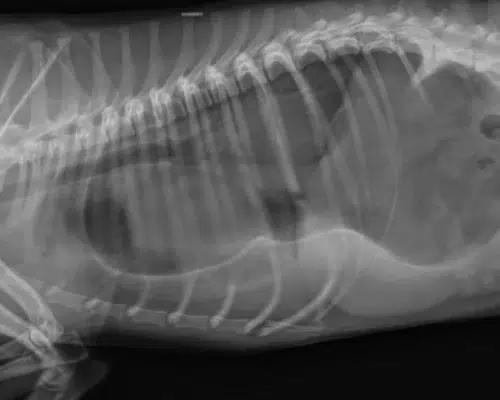

- Bildgebende Verfahren: Röntgen oder Ultraschall können verwendet werden, um strukturelle Anomalien, wie z. B. eine Caecum-Torsion oder Tumore, zu erkennen.